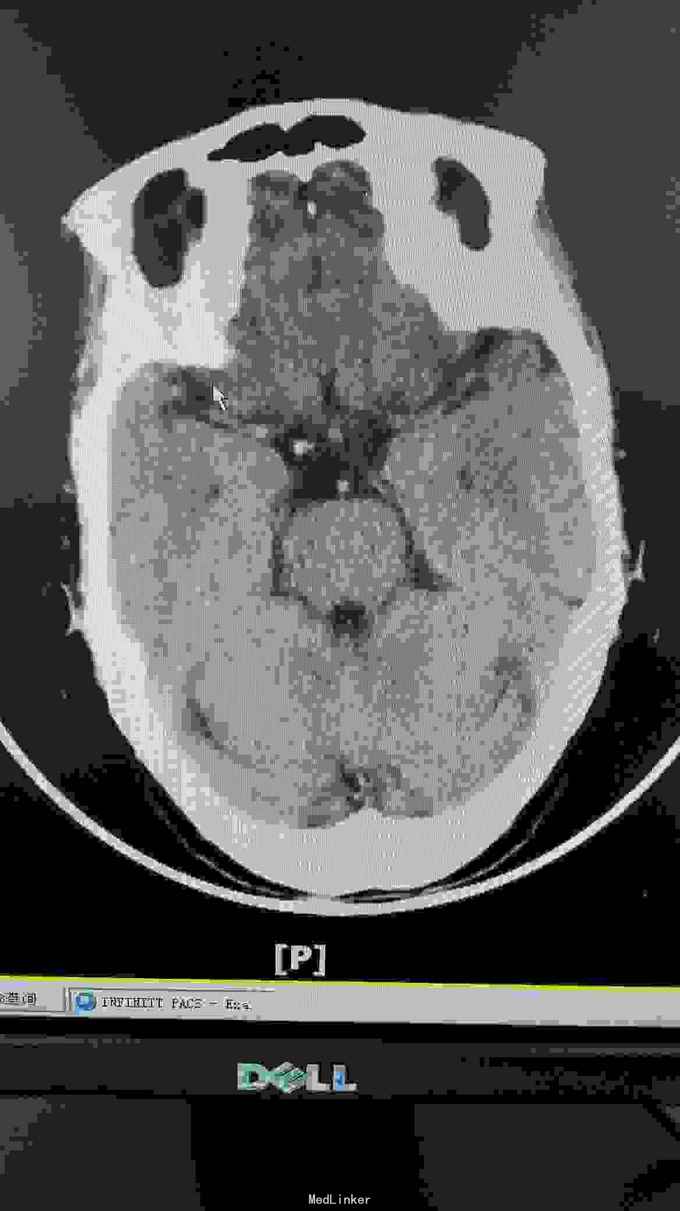

生命体征:耳温:36.8℃ 脉搏:96次/分 呼吸:20次/分 血压:140/67mmHg。pain score: 0/10 发育无异常,口唇无发绀,双肺呼吸音清,未闻及干湿性啰音;心率96次/分,律齐,未闻及明显病理性杂音;腹软,无压痛、反跳痛,肝脾肋下未及,双肾区无叩痛,双下肢无浮肿。神经专科:神清,构音尚清,双侧额纹对称,双眼睑下垂,右侧明显,双侧瞳孔等大等圆,直径约3.0mm,对光++,双眼活动尚可,伸舌居中,鼻唇沟无浅,颈软,四肢肌力5级,双侧肢体肌张力对称,双侧巴氏征未引出,双侧指鼻准,闭目难立征阴性。 血常规三系尚正常。出凝血系列,甲状腺功能 ;存在TSH偏高。肿瘤标志物基本正常范围。糖化血红蛋白正常范围;空腹血糖、血钾正常范围。大小便常规未见明显异常。 胸部CT提示右肺中叶及左肺上叶舌段纤维、增殖灶,请结合临床。颈动脉B超提示左侧颈动脉斑块形成,存在左侧颈动脉硬化。椎动脉B超提示双侧椎动脉未见明显异常。心超提示左室舒张功能下降。腹部B超提示肝、胆、胰、脾未见异常,双肾、输尿管、膀胱未见异常。甲状腺B超提示右侧甲状腺结节。肌电图提示重频试验阴性。心电图提示窦性心律,大致正常心电图。 这个病人因为做过钢板内固定术,所以磁共振没做!可惜了

诊断:双眼睑下垂待查:重症肌无力?动眼神经麻痹待排。2.高血压病?3.心功能不全? 目前治疗上予立普妥20mg调脂稳定斑块,待肌电图检查回报后余新斯的明口服,以及活血化瘀、改善循环等对症支持治疗.

这患者优先考虑重症肌无力,但是以单侧为主,所以动眼神经麻痹也需要排除,因为患者在上级医院做过“新斯的明试验”症状稍改善,持续数小时后又加重,所以等药效过了之后给她做了肌电图,重频试验阴性。1-5波幅下降不明显,结合头颅CT结果,诊断重症肌无力,予新斯的明口服后症状是有改善, 我想请教各位,单单从症状和新斯的明试验可以诊断重症肌无力吗?因为这个病人的肌电图表现是阴性的胸部CT也没看到有胸腺增生。